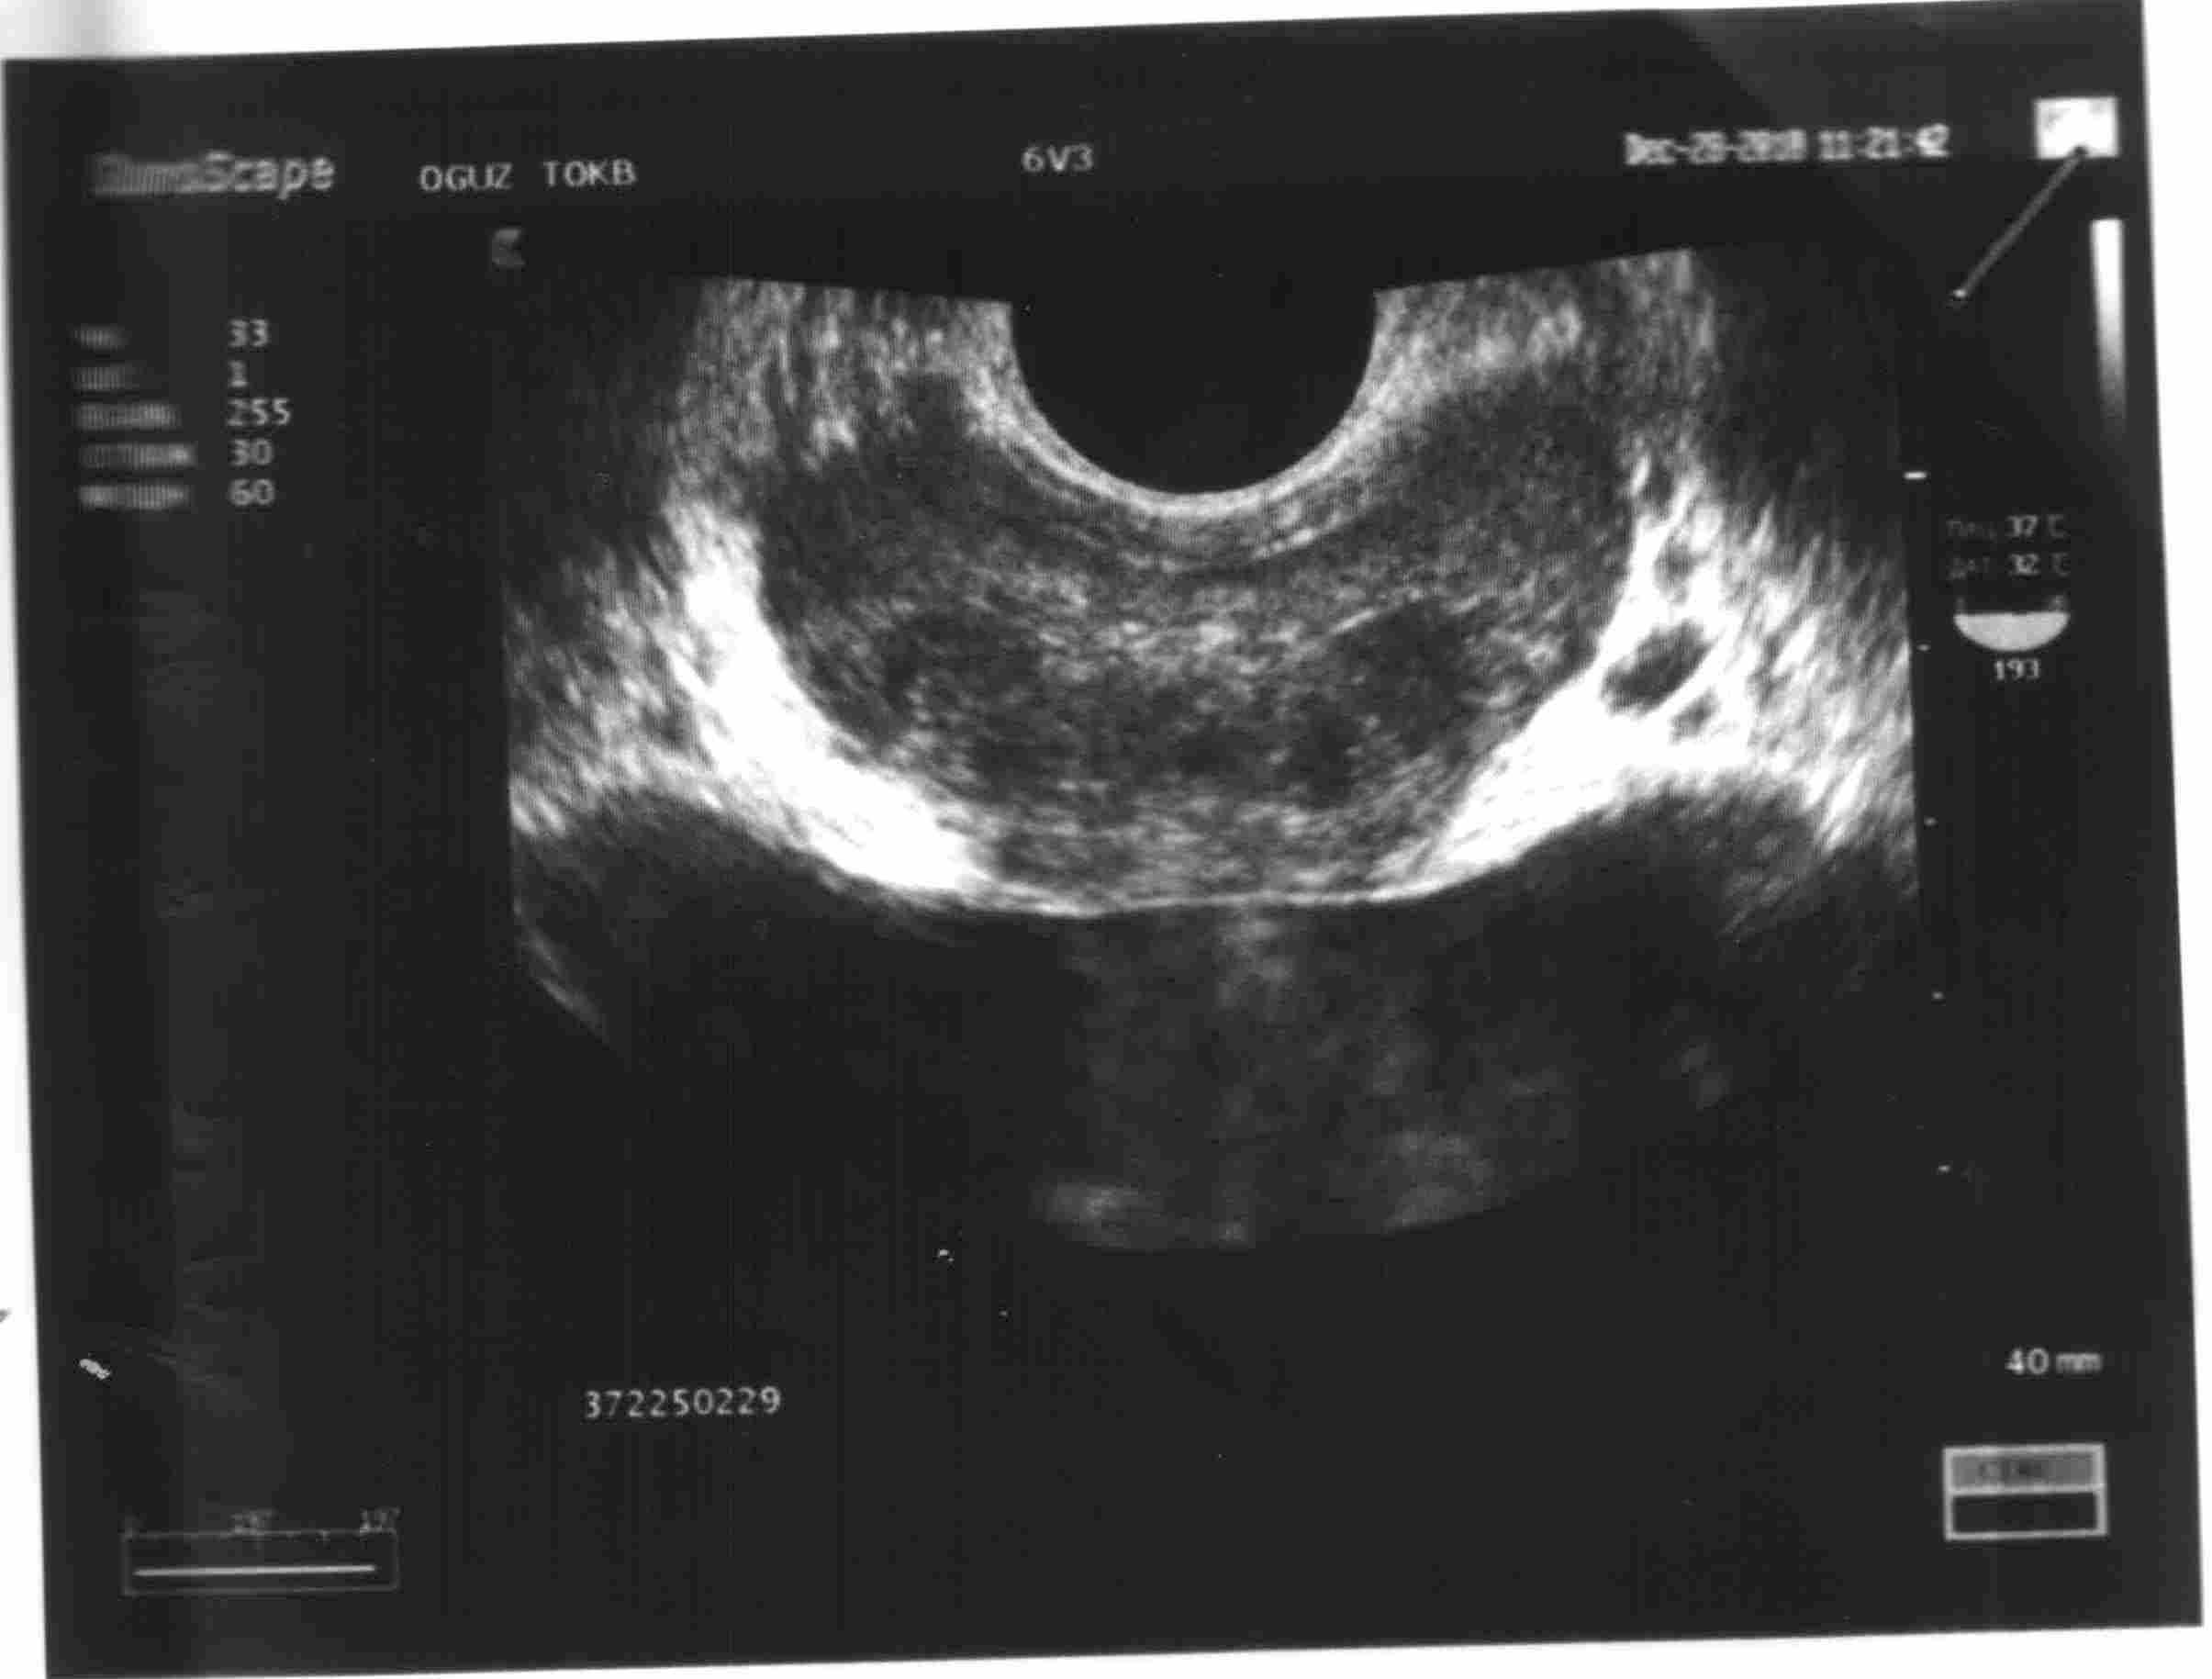

В мае 2012г. анализы на все ИППП (методами ПЦР и ИФА) были отрицательны, но улучшения состояния не последовало (слабость, запоры, шум в голове, потеря работоспособности, выпадение волос). В мае 2012г. обратился за консультацией в Областную инфекционную больницу. Было предложено сдать анализы на паразитов и гепатиты В и С, общ анализ крови, биохимия крови, УЗИ органов брюшной полости. Паразиты не были обнаружены, но был впервые выявлен гепатит В. Сдал количественный анализ, по его результатам менее 750 копий. Назначен препарат Фосфоглив в инъекциях и капсулах (3 месяца) + урсосан и циклоферон. Во время приема препарата состояние немного улучшилось, но проблемы с мочеполовой системой сохранились. Вновь сдал анализы на ЗППП в Кемерово – по прежнему были выявлены микоплазмы и хламидии. Анализ гормонов – тестостерон в норме. Частный уролог назначил Клацид СР, Орнидазол, Вобэнзим. На фоне приема Фосфоглива принимал АБ. К концу курса Фосфоглива и АБ стал себя чувствовать намного лучше (нормальная работа кишечника, работоспособность, пропал кашель и мокрота, меньше стала отекать слизистая носа). В начала сентября закончил курс Фосфоглива и антибиотиков. Недели 2 состояние было нормальное. Сдал биохимию крови, результаты в пределах нормы. Затем вновь состояние ухудшилось. Снизилась работоспособность, нарушение работы пищеварительного тракта (запоры), мочеполовой системы (нарушение мочеиспускания, снижение либидо). Начал принимать Урсосан (на ночь) + циклоферон (инъекции) по показаниям инфекциониста. Самостоятельно на фоне их приема начал принимать АБ левофлоксацин + макропен + ректально Вифирон (5 дн/2р). Заметил улучшение состояния при приеме Вобэнзима. Был на приеме у другого уролога, он назначил общий анализ крови, мочи, бак. посев мочи, мазок на гонококки, трузи предстательной железы. Общие анализы в норме (моча, кровь), незначительные диффузные изменения предстательной железы, объем не увеличен, есть кальцинаты. Бак посев – E coli. Уролог сказал, что такие результаты не могут влиять на потенцию и либидо.